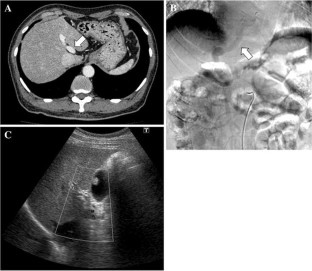

Patent ductus venosus (PDV) is a rare condition of a congenital portosystemic shunt from the umbilical vein to the inferior vena cava. This report presents the case of an adult patient with PDV, who was successfully treated with laparoscopic shunt division. A 69-year-old male was referred with hepatic encephalopathy. Contrast-enhanced CT revealed a large connection between the left portal vein and the inferior vena cava, which was diagnosed as PDV. The safety of a shunt disconnection was confirmed using a temporary balloon occlusion test for the shunt, and the shunt division was performed laparoscopically. The shunt was carefully separated from the liver parenchyma with relative ease, and then divided using a vascular stapler. Portal flow was markedly increased after the operation, and the liver function of the patient improved over the 3-month period after surgery. Although careful interventional evaluation for portal flow is absolutely imperative prior to surgery, a minimally invasive laparoscopic approach can be safely used for treating PDV.

Fig. 3